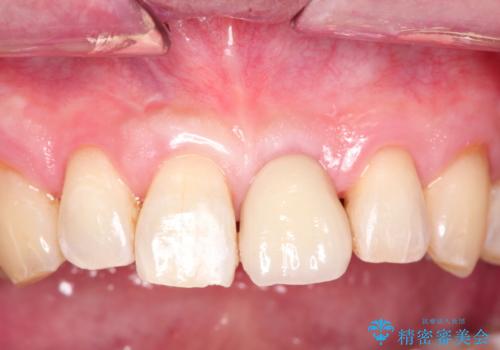

歯の表面に着色が付いて黄ばんで見えることがあるため、PMTCを行うとご自身の歯本来の色味にすることができます。

定期的にPMTCを行うことで綺麗な状態を維持することができます。

- 歯を白くする目的の施術ではありません